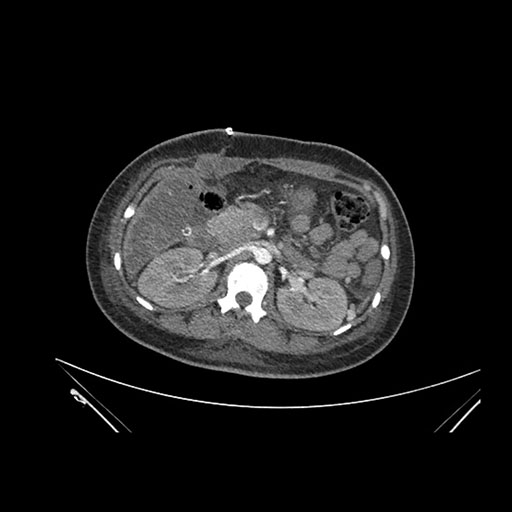

Axial Venous